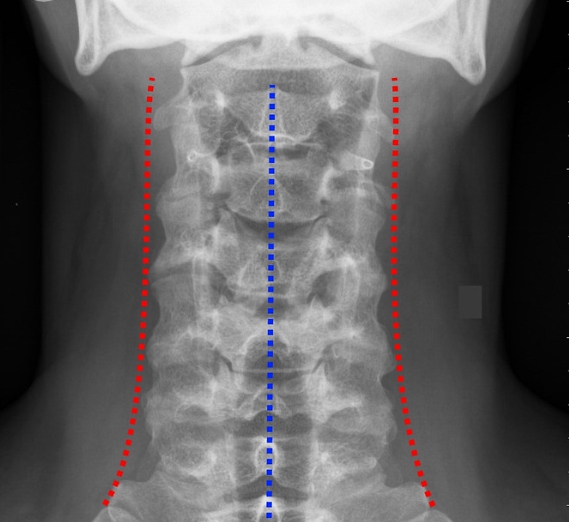

이석증에 좋다는 거 다 찾아보면서 양방, 한방 병원 다녀본 결과 거북목이나 S자 척추 틀어진 골반 이런 것들이 이석증에 영향을 준다는 분들이 있었습니다.

X-RAY

또한 장시간 앉아 있는 경우나 머리가 고정된 상태에서 움직임이 적으면 귀 안의 돌기가 제자리를 벗어나기 쉬워지기도 합니다. 잘못된 자세는 이석증 발병의 원이 되기도 합니다.